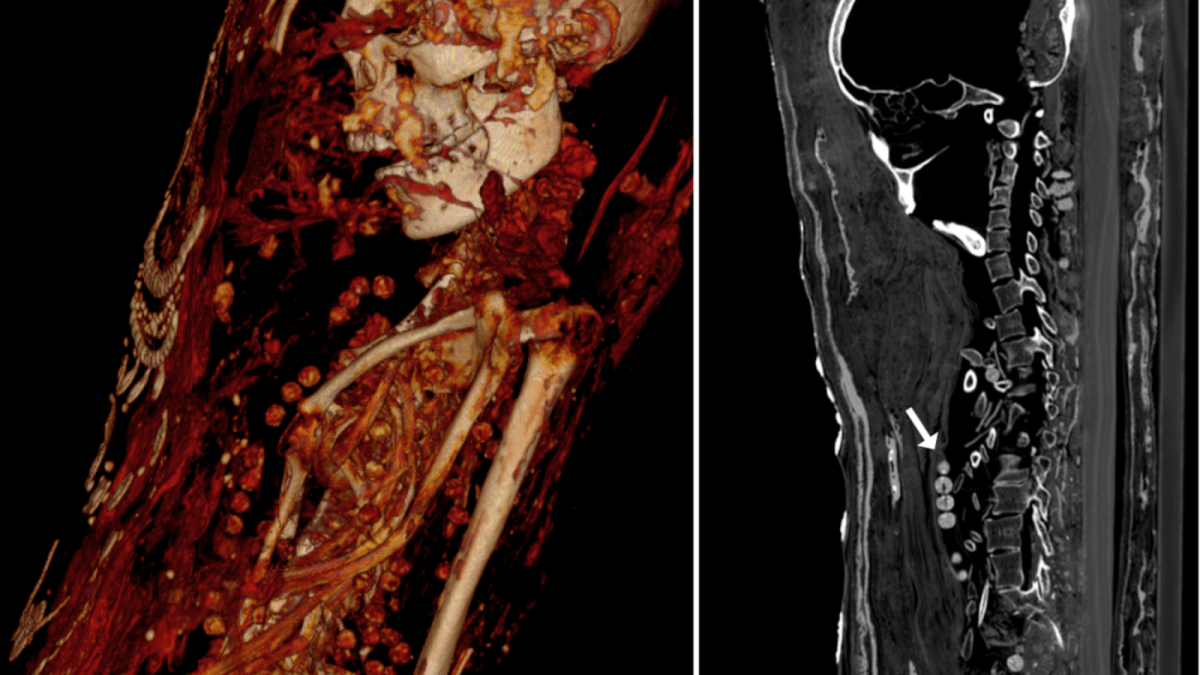

The CT scan shows that the man was between 25 and 30 years of age when he died and that he had several cavities and unerupted teeth. He was only 164 cm tall (around 5’4″). Several of his bones are broken, though this is believed to be the result of careless handling by whoever discovered the remains.

Most curiously, there is no evidence that his brain was removed during the mummification process, as was standard in other cases. It also seems that few embalming chemicals were used to preserve him. This suggests that he was just wrapped, painted, and buried and that dehydration is what kept his corpse so well preserved.

The woman was between 30 and 40 years old and stood at 151 cm (4’9″). She shows signs of arthritis in her knees. Like many other Egyptians, she was buried in fine jewelry. Several necklaces appeared on the scan, suggesting she was well off. For reasons unknown, nails were also found in her abdomen. Like her male counterpart, her brain was not removed during mummification, either.

The last mummy was that of a girl in her late teens. She showed signs of having a benign tumor on her back, and all of her internal organs were still intact. Her coffin contains hairpins, suggesting that she wore her hair up as depicted in her portrait.